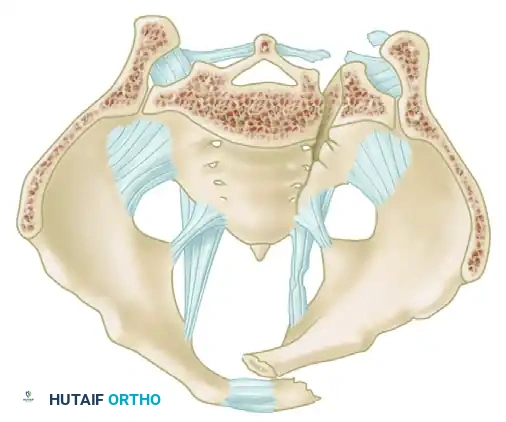

A profound understanding of pelvic osteoligamentous anatomy is the foundation of both classification and treatment. The pelvis is a ring structure composed anteriorly of the pubic and ischial rami connected at the symphysis pubis. A fibrocartilaginous disc separates the two pubic bodies, providing a degree of physiologic elasticity.

Posteriorly, the sacrum and the two innominate bones are joined at the sacroiliac (SI) joints. The SI joint itself possesses no inherent bony stability; its integrity relies entirely on a massive, complex ligamentous network.

The Posterior Tension Band

The posterior ligamentous complex is the primary weight-bearing and stabilizing structure of the pelvis. Tile famously compared the relationship of the posterior pelvic ligamentous and bony structures to a suspension bridge, with the sacrum suspended securely between the two posterior superior iliac spines.

The critical ligaments include:

* Interosseous Sacroiliac Ligaments: The strongest ligaments in the body, forming the primary restraint to vertical shear forces.

* Anterior and Posterior Sacroiliac Ligaments: Provide rotational stability to the SI joint.

* Sacrotuberous Ligaments: Resist rotation in the sagittal plane (flexion of the sacrum).

* Sacrospinous Ligaments: The primary restraints to external rotation of the hemipelvis.

* Iliolumbar Ligaments: Connect the L5 transverse process to the iliac crest, augmenting vertical and rotational stability.

Biomechanical Restraints

Pelvic stability is determined by these ligamentous structures acting across various planes. The primary restraints to external rotation (the "open book" deformity) are the ligaments of the symphysis, the sacrospinous ligament, and the anterior sacroiliac ligament. Vertical displacement of the hemipelvis is controlled by all the aforementioned structures. However, if the anterior structures are disrupted, vertical stability may still be maintained by intact interosseous sacroiliac, posterior sacroiliac, and iliolumbar ligaments.

Surgical Warning: A rotationally unstable hemipelvis may remain vertically stable due to an intact posterior tension band. Recognizing this distinction is paramount, as it dictates whether the patient requires simple anterior stabilization or complex posterior ring reconstruction.

Type B: Rotationally Unstable, Vertically Stable

* B1 (Open Book): External rotation or anteroposterior compression forces disrupt the symphysis and anterior SI ligaments. The posterior interosseous ligaments remain intact, preventing vertical shear.